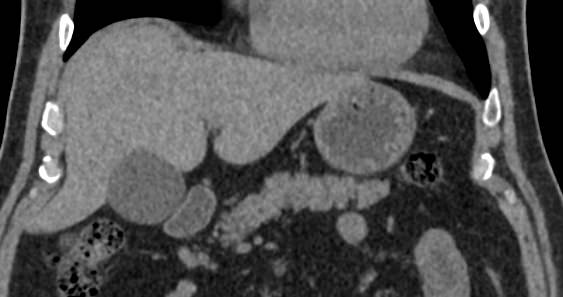

Современным высокоинформативным способом выявления патологических изменений поджелудочной железы является мультиспиральная компьютерная томография с прицельным сканированием органа.

При помощи специальных цифровых приложений данные, полученные при сканировании, преобразуются в трехмерные изображения органа, что дополнительно повышает точность и достоверность диагностики заболеваний поджелудочной железы.

Контрастирование позволяет отличить зоны воспаления, деструкции, разрастания фиброзной ткани и опухолевой трансформации от сохраненной паренхимы поджелудочной железы. КТ поджелудочной железы с контрастированием дает исчерпывающую информацию о состоянии органа и патологических процессах в нем.

Что покажет КТ поджелудочной железы

- злокачественные и доброкачественные опухоли, включая инсулиному, глюкагоному, випому, гастриному, рак поджелудочной железы;

- кальцинаты в панкреатических протоках;

- острую и хроническую формы панкреатита;

- кисты и псевдокисты поджелудочной железы